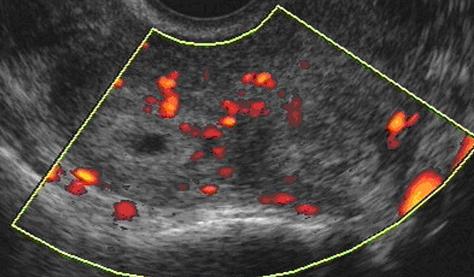

Допплер УЗИ при беременности

Допплер УЗИ делается так же, как и УЗИ органов малого таза, но оно изучает движение крови по сосудам. Этот метод был использован для исследования беременных женщин с 1977 года, в первую очередь обследовали кровь, которая оттекает через пуповину. С 1980-х годов этот метод также был использован для того, чтобы посмотреть кровоток между маткой и плацентой. Оба теста служат для оценки функционирования плаценты и самочувствия ребенка. Допплеровская флоурометрия использует волны более высоких интенсивностей, чем абдоминальное и вагинальное УЗИ матки, и при этом обеспечивается непрерывность подачи волны.